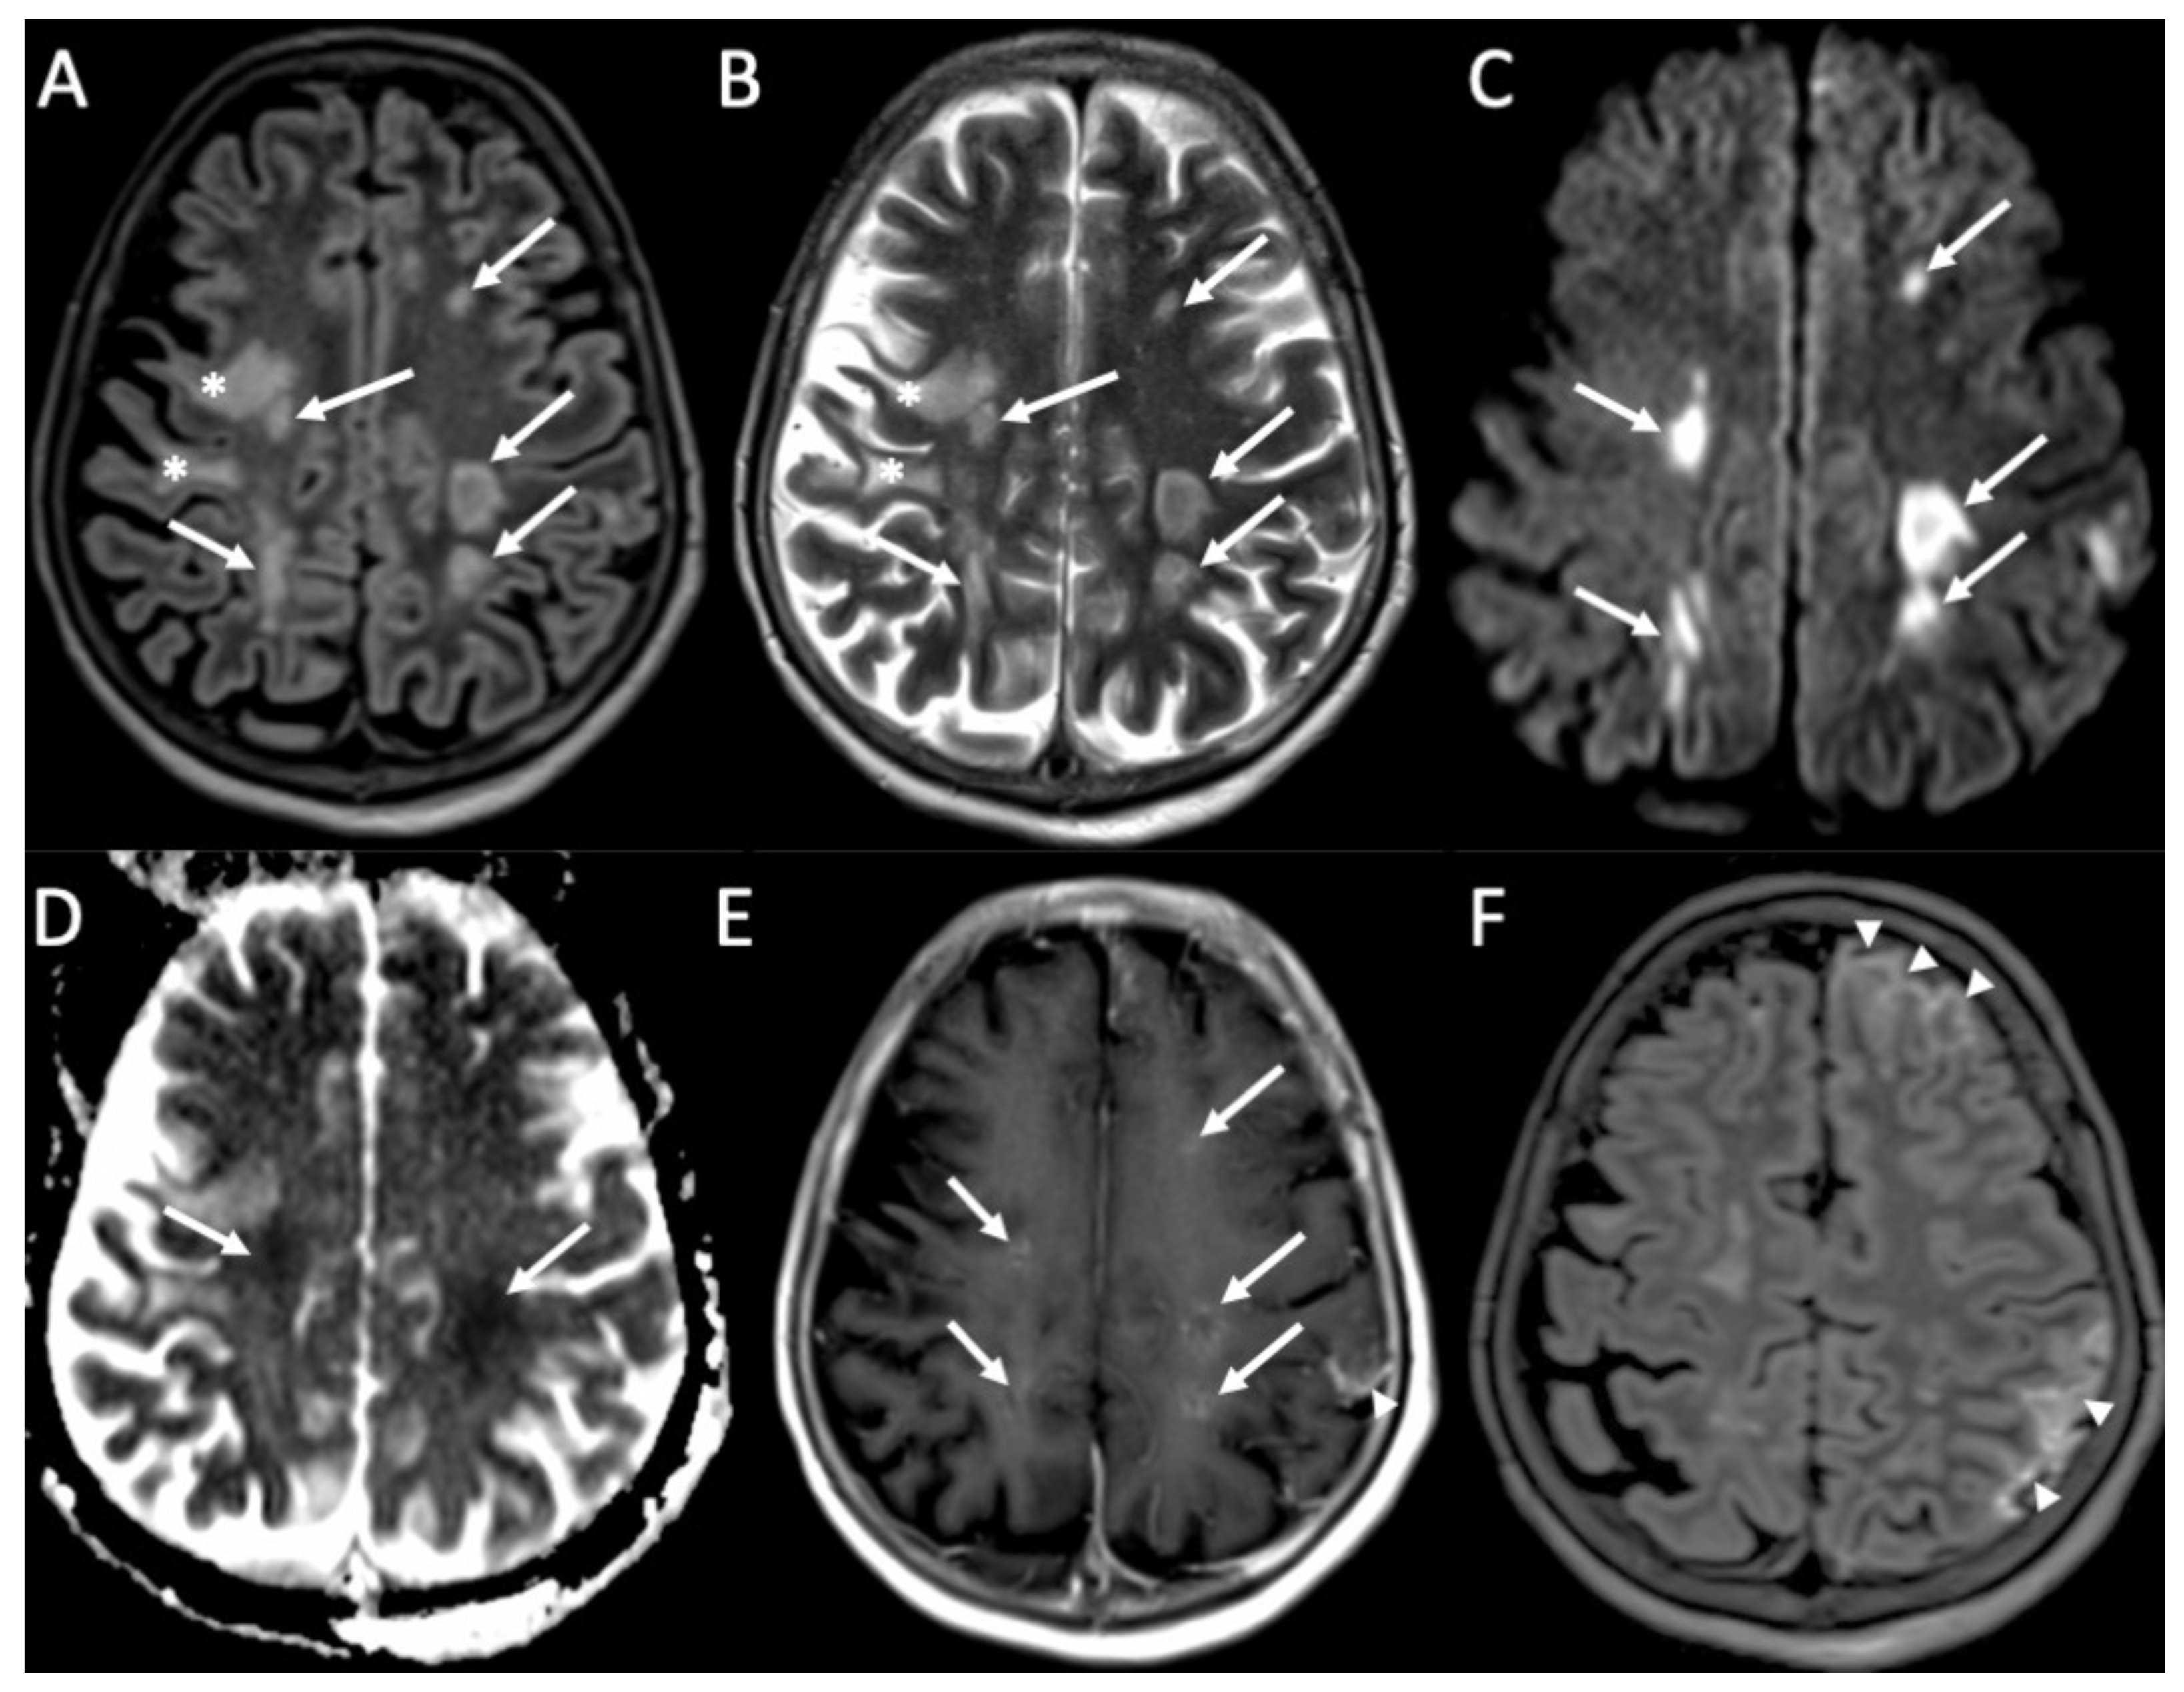

Figure 4.

Axial FLAIR (A), T2 (B), DWI (C), ADC (D), enhanced T1 (E), and FLAIR (F) of a patient with Streptococcus Pneumoniae depict multiple recent ischemic areas in the white matter in the fronto-parietal regions bilaterally (arrows in A–E), which are hyperintense on FLAIR and T2, show restricted diffusion and faint contrast enhancement. There is also a leptomeningeal enhancement in the right frontal and parietal regions (arrowheads in E,F). Note also a gliotic area in the right frontal region (*) due to a known previous ischemic event.